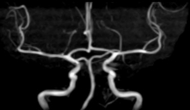

頭部MRI・頭部MRA・頚部MRA